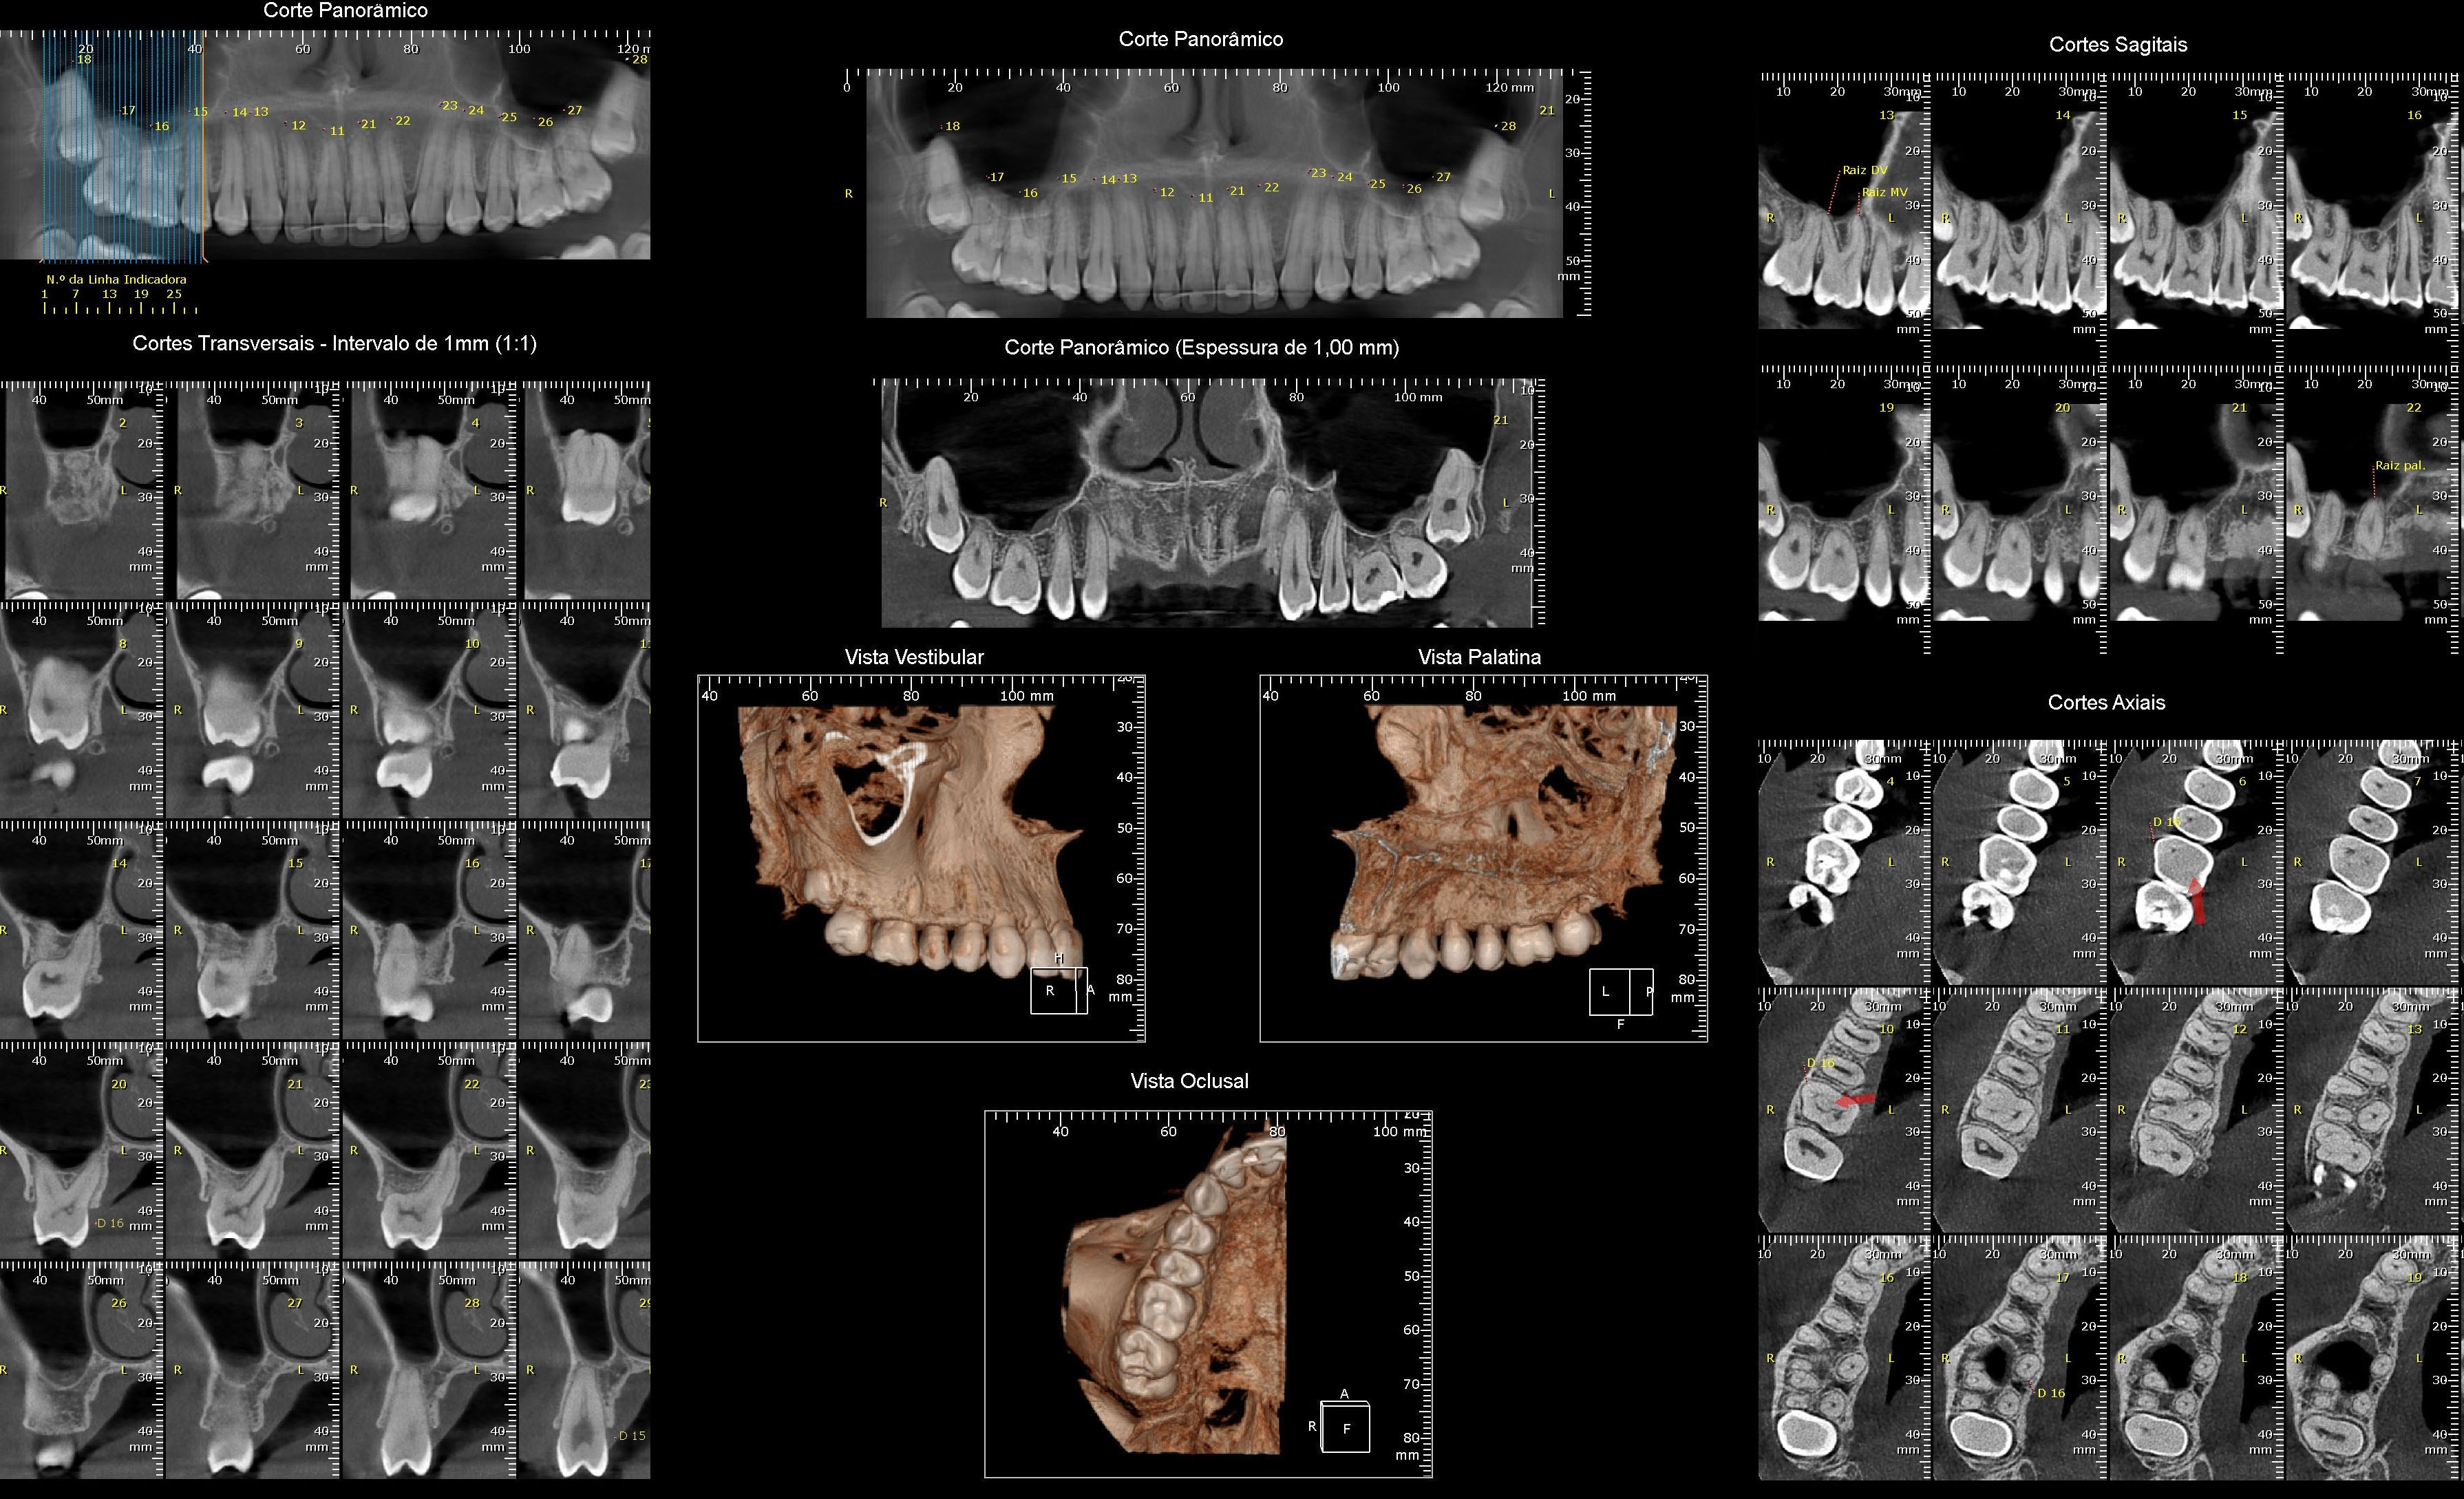

RADIOGRAFIAS DIGITAIS

Radiografia Panorâmica

Telerradiografia Lateral / Frontal

Radiografia Periapical

Radiografia Oclusal

Radiografia de ATM

DOCUMENTAÇÃO ORTODÔNTICA

Laudos e Análises Cefalométricas

Fotografias Bucais e Faciais

Modelos de Estudo

Documentações Digitais (Consultório Virtual)